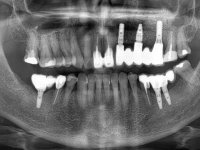

66-year-old male patient, non-smoker. It featured a 5-member metal-ceramic bridge with extreme mobility. Teeth 11 and 21 had infiltrated cervical margins. Both arches showed root exposure with signs of cervical abrasion. Composite resin “slots” were visible on the buccal surfaces of some mandibular teeth compatible with an orthodontic treatment with aligners that the patient was undergoing. After the imaging examination, it was found that the bridge's distal support, tooth 24, was irretrievably lost. The mesial pillars 11 and 21 had endodontic treatment and intraradicular posts. Teeth 25 and 26 also had endodontic treatment and extensive restorations in composite resin. In the lower jaw, two bridges were visible. In the third quadrant a 4-element bridge supported on tooth 35 and on 2 implants placed in the location of teeth 36 and 37. In the fourth quadrant a 3-element bridge supported on tooth 45 and an implant placed in the location of tooth 46. The patient presented a thick gingival phenotype and very good oral hygiene.

The patient was proposed to undergo a fixed oral rehabilitation consisting of a 2-element bridge over teeth 11 and 21 and a 5-element bridge over 3 implants that would be placed in the location of teeth 22, 24 and 26. The prosthetic structures would have an infrastructure in Zr coated with ceramic and the bridge over the implants would be screwed. The indicated extraction of teeth 25 and 26 and placement of an implant in the 26 site would imply surgery to fill the maxillary sinus. As the patient showed interest in having fixed temporary rehabilitation during treatment, we divided the treatment into 6 phases to achieve this goal: 1- Placement of a temporary bridge over teeth 11,21,25 and 26. With tooth extraction 24. 2- Placement of 2 implants in the location of teeth 22 and 24. 3- Placement of a temporary 6-element bridge over teeth 11 and 21 and over the implants. 4- Carrying out surgery to fill the maxillary sinus. 5 – Placement of the implant in the location of tooth 26 and in the area where the filling of the maxillary sinus was made. 6 – Placement of the definitive work.

A temporary acrylic bridge made in the laboratory with 7 elements was made, with teeth 11,21, 25 and 26 as pillars. The old bridge was removed and tooth 24 was extracted. The provisional bridge after relining was cemented in the mouth. Two implants were placed in the teeth 22 and 24 and 3 months after this intervention an impression was made to make a temporary bridge screwed over the implants and cemented to the teeth. The bridge was placed in the mouth and teeth 25 and 26 were extracted. 3 months later, surgery was performed to fill the maxillary sinus and 6 months later the implant was placed in the location of tooth 26. After osseointegration of this implant, the final impression was made for the final work. The bridge over the implants was permanently screwed on and the bridge over the teeth was cemented with resin-reinforced glass ionomer cement.